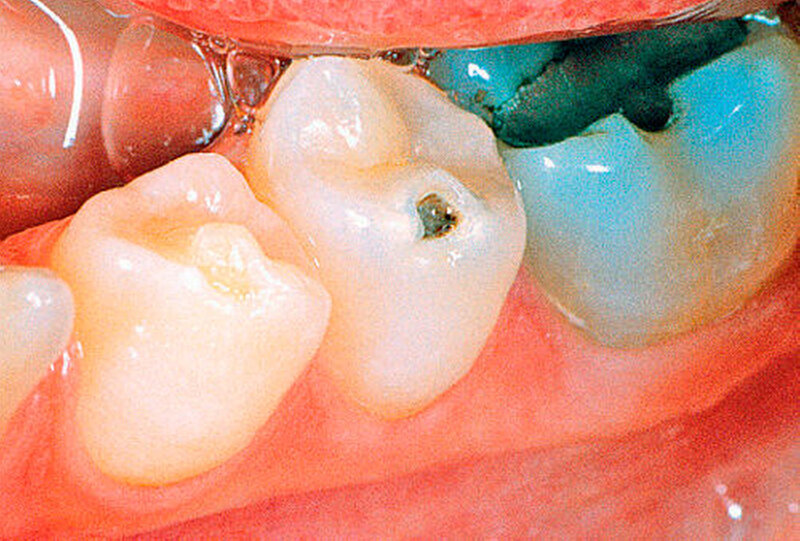

Zuerst bilden die vorhandenen Odontoblasten normales Dentin. Später werden die Odontoblasten zunehmend durch mesenchymale Zellen ersetzt, welche atypisches Dentin mit irregulär verlaufenden Dentintubuli bilden (Abbildungen 7a, b und 9). Die Dentinogenesis imperfecta führt zu einer blaubraunen Verfärbung der Milchzähne und zu einer bernstein-/perlmuttartigen Verfärbung der permanenten Zähne (Abbildungen 5, 6a,b und 8). Das vorhandene Dentin ist weicher als normal. Die histologischen Schnitte zeigen eine oft wellige Schmelz-Dentin-Grenze, was auf einen Defekt des Schmelz-Dentinverbundes schließen lässt (Abbildung 10). Infolge der mangelhaften Schmelz-Dentinverbindung splittert häufig Schmelz ab. Diese Schmelzabsplitterungen können zu Kariesbildung an atypischer Lokalisation führen (Abbildungen 6a, b). Zudem unterliegen die Zähne einer erhöhten Attrition. Irreguläre Dentinbildung kann nach dem Zahndurchbruch die gesamte Pulpakammer obliterieren. Beim gleichen Patienten können jedoch vollständig obliterierte neben normalen Pulpakammern beobachtet werden.

Die betroffenen Zähne weisen gelbbraune Verfärbungen auf (Abbildungen 11, 12 und 14) und sind kleiner als normal. Der vorhandene Schmelz ist hypoplastisch und unterverkalkt. Schmelz und Dentin sind sehr weich. Die Zahnkronen sind missgebildet. Die Wurzeln sind in der Regel sehr kurz. Die Zahnoberfläche kann Furchen, Eindellungen und Grübchen aufweisen. Der Durchbruch und die Wurzelbildung der befallenen Zähne sind verzögert. Infolge der stark veränderten Zahnhartsubstanz ist eine stark erhöhte Kariesanfälligkeit vorhanden. Kurz nach dem die betroffenen Zähne die Gingiva durchbrochen haben, kann es deshalb rasch zur Kariesbildung kommen. Daraus resultieren häufig Pulpanekrosen und Abszesse.